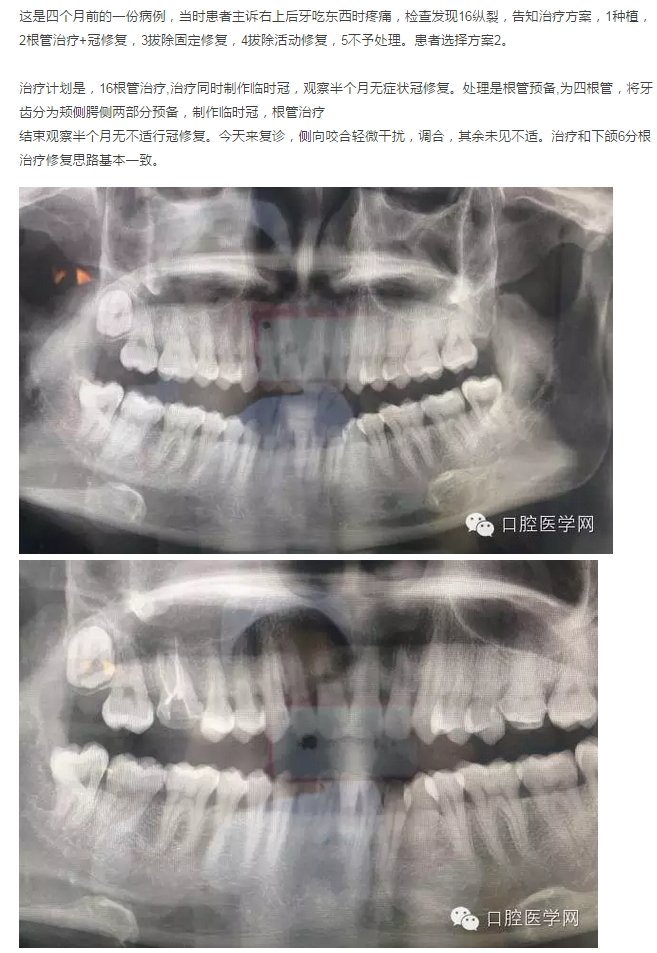

1例16縱裂的治療

案情介紹